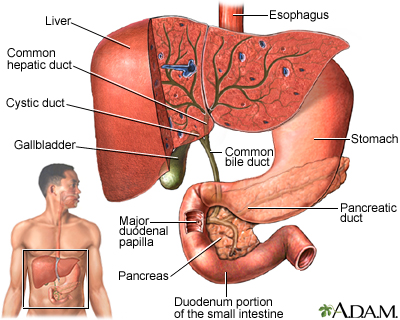

Bile and the Gallbladder

The formation of gallstones is a complex process that starts with bile, a fluid composed mostly of water, bile salts, lecithin (a type of phospholipid), and cholesterol. Most gallstones are formed from cholesterol.

- Bile is important for the digestion of fat. It is first produced by the liver and then secreted through tiny channels that eventually lead into a larger tube called the common bile duct, which leads to the small intestine.

- Only a small amount of bile drains directly into the small intestine, however. Most flows into the gallbladder through the

cystic duct

, which is a side branch off the common bile duct. This system of ducts through which bile flows is called thebiliary tree

.

- The gallbladder is a 3 to 4-inch (7 to 10 cm) sac with a muscular wall that is located under the liver. Here, most of the fluid is removed from the bile (about 2 to 5 cups, or 0.6 to 1.2 liters of bile gets produced by the liver in a day), leaving only a few tablespoons of concentrated bile.

- The gallbladder serves as a reservoir until bile is needed in the small intestine to digest fats. This need is signaled by a hormone called

cholecystokinin

, which is released when food enters the small intestine. - Cholecystokinin causes the gallbladder to contract and deliver bile into the intestine. The force of the contraction propels the bile down the common bile duct and into the small intestine, where it emulsifies (breaks down) fatty molecules.

- This part of the digestive process enables the emulsified fat, along with important fat-absorbable nutrients (such as vitamins A, D, E, and K), to pass through the intestinal lining and enter the bloodstream.